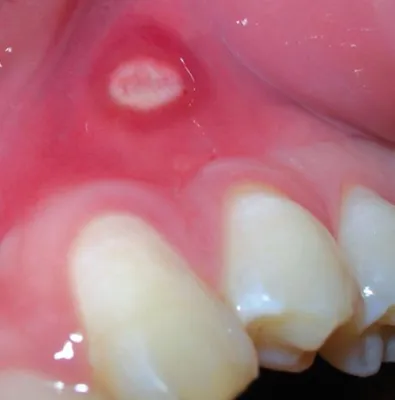

Aphthen haben ein typisches Aussehen, wodurch uns die Diagnose relativ einfach fällt: kleine, gelb-weißliche Stippen oder Bläschen auf hochrotem Untergrund, der sich ringförmig um die weiße Mitte zieht. Ihre Größe schwankt von 1 bis zu 30 mm.

Schauen Sie in den Spiegel lassen sich die Aphthen durch ihr typisches Aussehen schnell als Aphthen identifizieren: eine linsenkern-große (meist 1 - 5mm) kleine, weiße oder gelbliche Stelle oder Bläschen, umgeben von einem stark geröteten Hof.